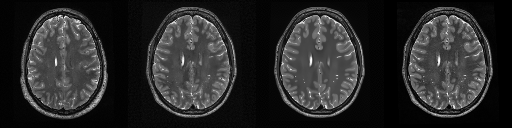

HCP T2w dataset

We utilize images from the publicly available Human Connectome Project (HCP) [51] T2-weighted (T2w) images dataset for the task of compressed sensing, which contains brain images from 47 patients. The HCP dataset includes cross-sectional images of the brain taken at different levels and angles.

Compressed sensing

We train a flow-based model from scratch on 10,000 randomly sampled images, utilizing the ncsnpp architecture [9] with minor adaptations for grayscale images. We employ compression rates , meaning . The measurement operator is given by a subsampled Fourier matrix, whose sign patterns are randomly selected. We evaluate our reconstruction algorithm’s performance on 200 randomly sampled test images.

We present the quantitative and qualitative results of compressed sensing in Tab. 1 and Fig. 4, respectively. As shown in Tab. 1, our method consistently achieves the best performance across varying compression rates . In Fig. 4, our method produces reconstructions that are more faithful to the original images, with fewer artifacts, leading to higher accuracy and clearer details.